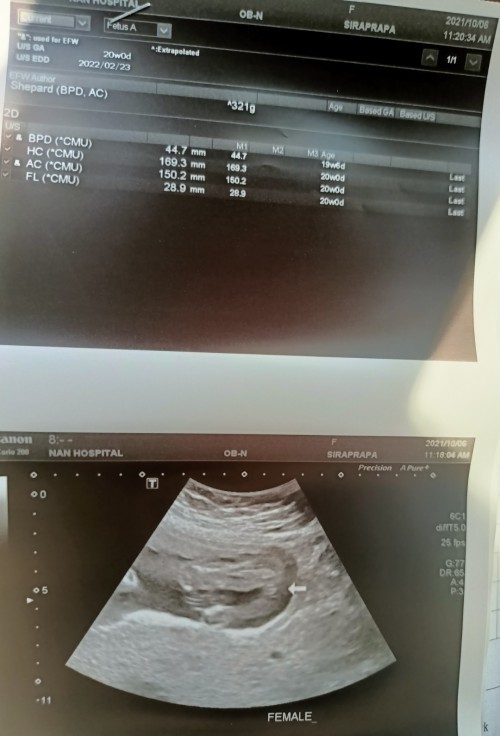

ภาพซาวด์ดูเพศล่าสุดตอน20วีคค่ะ ตอนนี้23วีคแล้ว